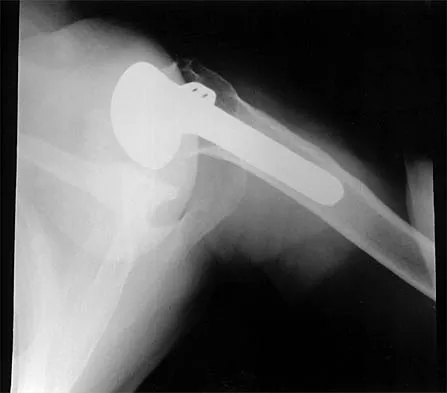

During total shoulder replacement for rheumatoid arthritis, fracture of the humeral shaft occurs. An intraoperative radiograph shows a displaced short oblique fracture at the tip of the prosthesis. At this point, the surgeon should

Explanation

The risk of intraoperative fracture in osteopenic rheumatoid bone is significant. Fractures may occur with dislocation of the head and canal reaming, especially while extending and externally rotating the shoulder. If the fracture occurs at the distal tip of the prosthesis, the use of a long-stemmed prosthesis to bypass the fracture site and supplementation with wire cables has been reported with good results. Wright TW, Cofield RH: Humeral fractures after shoulder arthroplasty. J Bone Joint Surg Am 1995;77:1340-1346. Boyd AD Jr, Thornhill TS, Barnes CL: Fractures adjacent to humeral protheses. J Bone Joint Surg Am 1992;74:1498-1504.